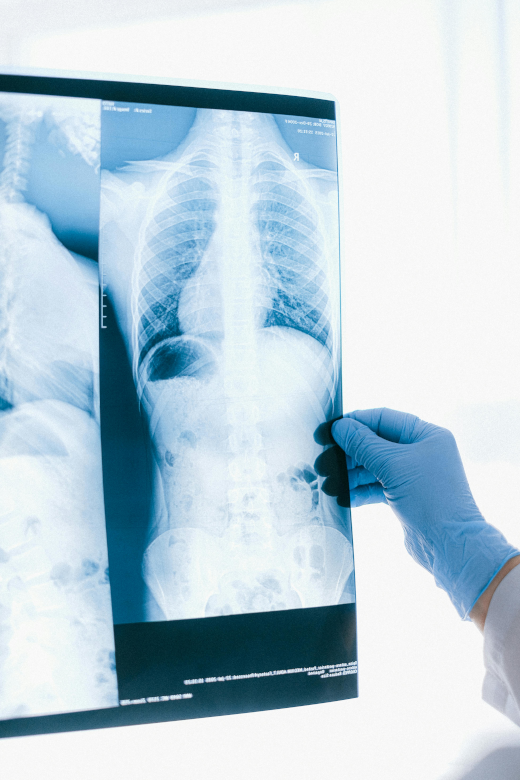

• radiographie

Radiologie

Radiographie standard numérique

Examen rapide et précis pour l’analyse des structures osseuses et pulmonaires.